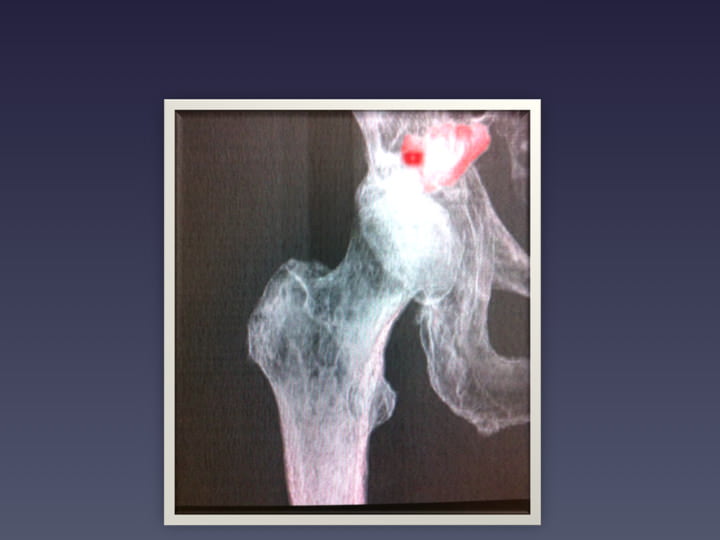

• BASSIN HANCHE

• FRACTURES DU BASSIN

• OSTEOPLASTIE ET OSTEOSYNTHESE SOUS GUIDAGE SCANNER

• OSTEOSYNTHESE

• RSNA 2012 VISSAGE DES FRACTURES COTYLOÏDIENNES

• OSTEOSYNTHESE SOUS SCANNER